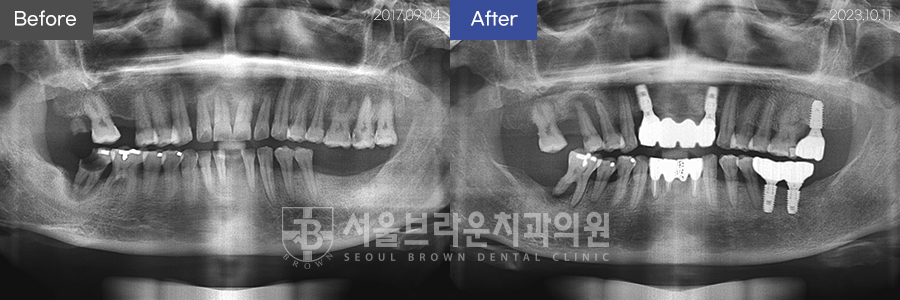

임플란트 | 50대 / 여 / 상하악임플란트

50대 / 여 / 상하악임플란트